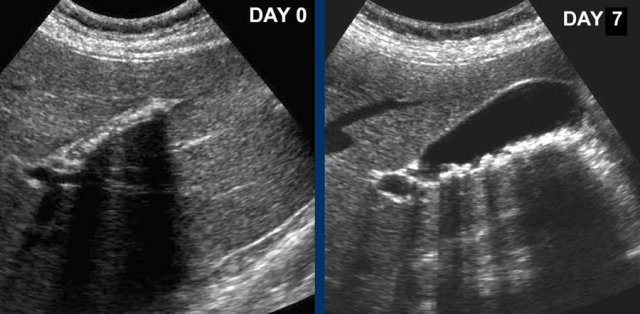

At day 0 there is acute hydrops due to an impacted stone.

One day later, the patient is symptom free.

The stone is still in place, but apparently allows passage of bile to the cystic duct, since hydrops has disappeared.

Reperfusion edema and sludge are the silent witnesses of the previous attack .

CRP remained normal.